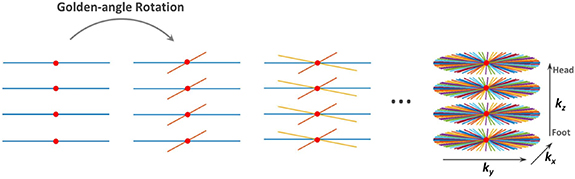

The MR pulse sequence used in this work represents Cartesian encoding over kz and a stack of stars trajectory with radial sampling over kx–ky (Usman et al 2013) (figure 3). The radial sampling angle is the golden angle ∼111.25°. The sampling motion artifacts are averaged out by oversampling the center of k-space in the radial sampling. This oversampling may lead to an overweighting of low frequencies so a density compensation is applied where it serves the same aim as a ramp filter (Fessler 2019):

Figure 3. Continuous acquisition of spokes with 3D stack-of-stars. Radial encoding in the kx–ky planes and fully-sampled Cartesian on the kz dimension. Red dots represent the k-space center from which the respiratory motion signal was extracted (Feng et al 2014).